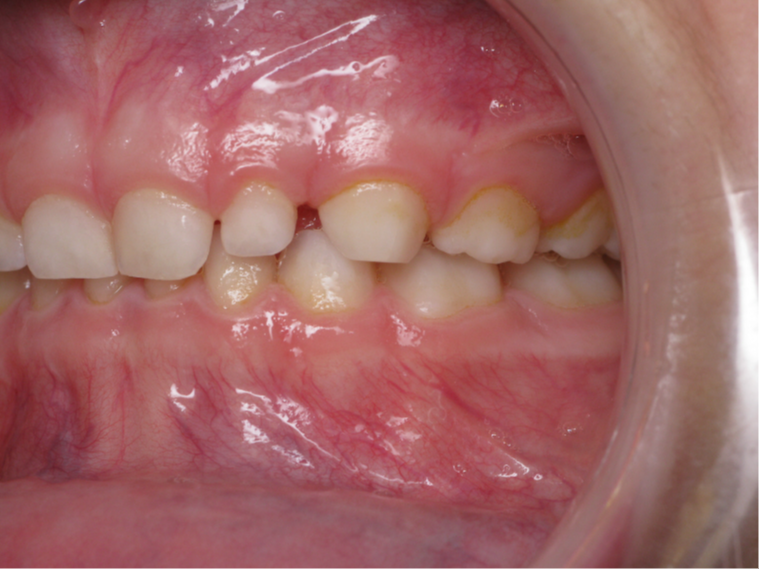

inversion des dents postérieur coté gauche

traitement actif multibagues

bilan début et fin de traitement